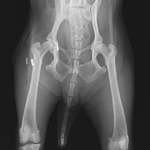

16歳のToy poodleさんが右の股関節を脱臼(背側前方)したとの事で主治医の先生から連絡がありました。1.9 Toggleとタイクロン(USP2)で整復術を実施しました。高齢ながら頑張ってくれました。2週間の安静期間が必要です。